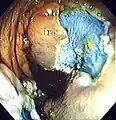

Polyp is identified.

A sterile solution is injected under the polyp to lift it away from deeper tissues.

A portion of the polyp is now removed.

The polyp is fully removed.